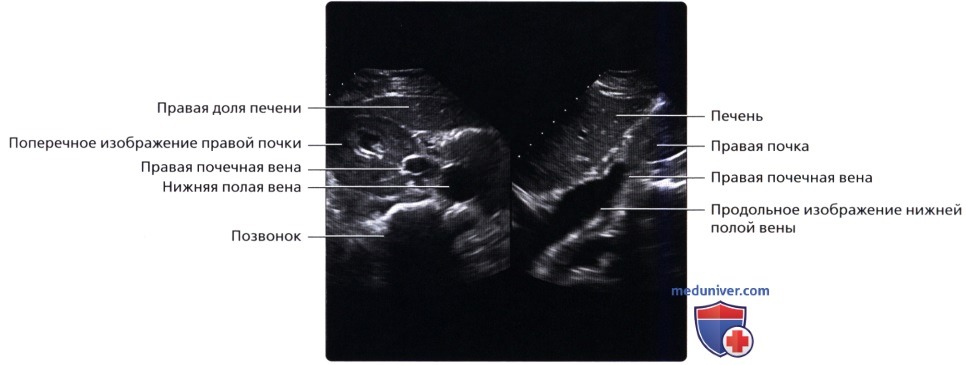

Сначала исследуют почки в продольном направлении (поясничная область), затем изучают поперечные и косые срезы, перемещая датчик на переднюю и боковые поверхности живота. При этом пациента просят поочередно повернуться на правый и левый бок. Такая техника позволяет определить локализацию (месторасположение) почек, их размеры и форму, оценить состояние паренхимы, почечных синусов, чашечек и лоханок.

Для определения подвижности почек и улучшения визуализации органов при каждом изменении положения тела врач просит больного вдохнуть и на несколько секунд задержать дыхание. На вдохе почки опускаются из-под реберной дуги и просматриваются намного лучше. УЗИ почек стоя делают при подозрении на нефроптоз (опущение одной или обеих почек).

• Забрюшинные структуры бобовидной формы с четким контуром, смещающиеся при дыхании

• Правая почка:

о Печень используется в качестве акустического окна

о Датчик устанавливается в подреберье или в межреберный промежуток

о Выполняйте исследование при различной глубине вдохе

о Попросите пациента немного повернуться влево, приподняв правый бок и выполняйте сканирование с боковой/заднебоковой поверхности

• Почечные вены:

о Лучше всего визуализируются при поперечном трансабдоминальном сканировании

о Также могут быть видны при сканировании в фронтальной плоскости с заднебоковой поверхности